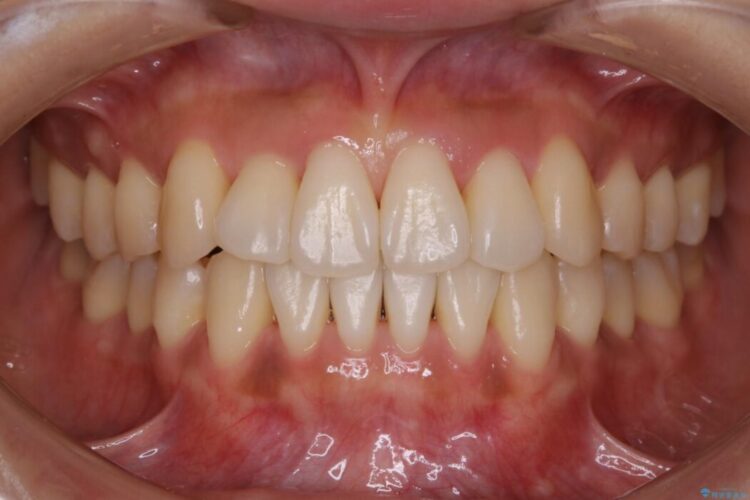

前歯のガタガタを気にされて来院されました。

検査の結果、骨の厚みに余裕がないことが判明しましたので、幅の拡大と歯の側面を削るIPRでは歯周病に対する不安を拭いきれないと判断しました。

よってマイクロインプラントを用い、奥歯から順番に遠心移動させることによってスペースを確保することにしました。

歯を後方に移動させてスペースを確保する場合、マウスピースの装着時間に加えて装着時の適合度が良い状態に保たれているかが鍵となります。

歯は戻ろうとする力が強いためマウスピースの装着をしっかりしていただけなかった場合は、作り直しや治療の長期化につながってしまう可能性があります。